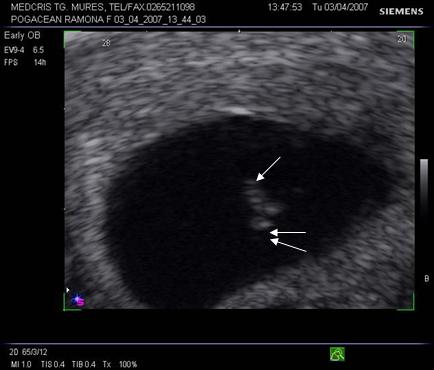

8.Sarcina si dispozitivul intrauterin

Pacienta purtatoare de IUD va fi examinata pentru a stabili locul dispozitivului in cavitatea uterina. Daca acesta a fost evacuat sarcina va continua fara risc. Daca IUD este inca intracavitar, va trebui decis daca trebuie extras in functie de pozitie si de varsta sarcinii.

Ecografic, dispozitivul apare ca o structura ecogena cu forma variabila, localizat alaturi deasupra sau sub sacul gestational, eventual in canalul cervical.

Daca dispozitivul intrauterin prin pozitia sa nu poate fi extras, continuarea sarcinii poate fi grevata de cresterea riscului de avort, infectii, perforatii, nasteri premature. Prezenta asocierii IUD cu sarcina nu constituie indicatie de avort si nu creste riscul de anomalii fetale.

La pacientele cu teste pozitive si IUD prezent se va cerceta cu grija regiunea anexiala bilateral pentru a exclude o sarcina ectopica.

Fig nr. 90. Dispozitiv intrauterin dislocat in col, la o sarcina de 17 saptamani